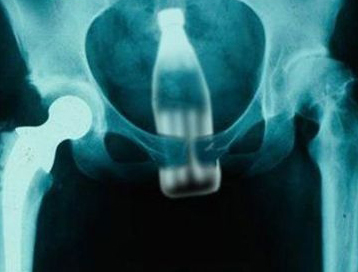

이와 함께 동팡왕은 여성의 국부에 들어간 이물질을 빼내기 위해 병원의 찾는 여성들의 수가 적지 않다고 보도하면서 병원측으로 부터 입수한 다양한 엑스레이 사진을 함께 게재하여 중국 독자들의 관심을 끌고 있다.

[사진]여성의 몸에서 제거한 계란(위), 병원 측이 제공한 다양한 여성 환자들의 엑스레이 사진 / 출처=중국 인터넷